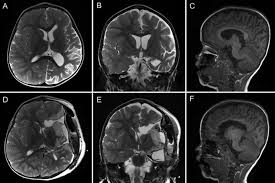

Здравствуйте!Беспокоит постоянная головная боль в области лба и в виске слева и звон в левом ухе.Боль монотонная и пульсирующаяОбезболивающие не помогают.Неврологи ставили диагноз мигрень,делал уколы иринекс,пил таблетки от мигрени ,ничего не помогает.Также лечили внутричерепное давление тоже не помогло(пирацетам,магнезий,актовегин,диакарб)В левой височной области имеется архоинодальная киста 36х10х17 мм.Также расширены периневральные пространства зрительных нервов.Глазное давление в нормеМожет ли данная киста быть причиной головной боли ?

Снимки мртhttps://drive.google.com/file/d/1sbWERelK3rUJm4z0P7nltAPZVu9NX0md/view?usp=drivesdk

Здравствуйте!Прикрепил заключение. Не пойму как полностью отправить сами снимки МРТ Может сможете через Mail облако посмотреть https://cloud.mail.ru/public/9f6x/xjqpBSKLt